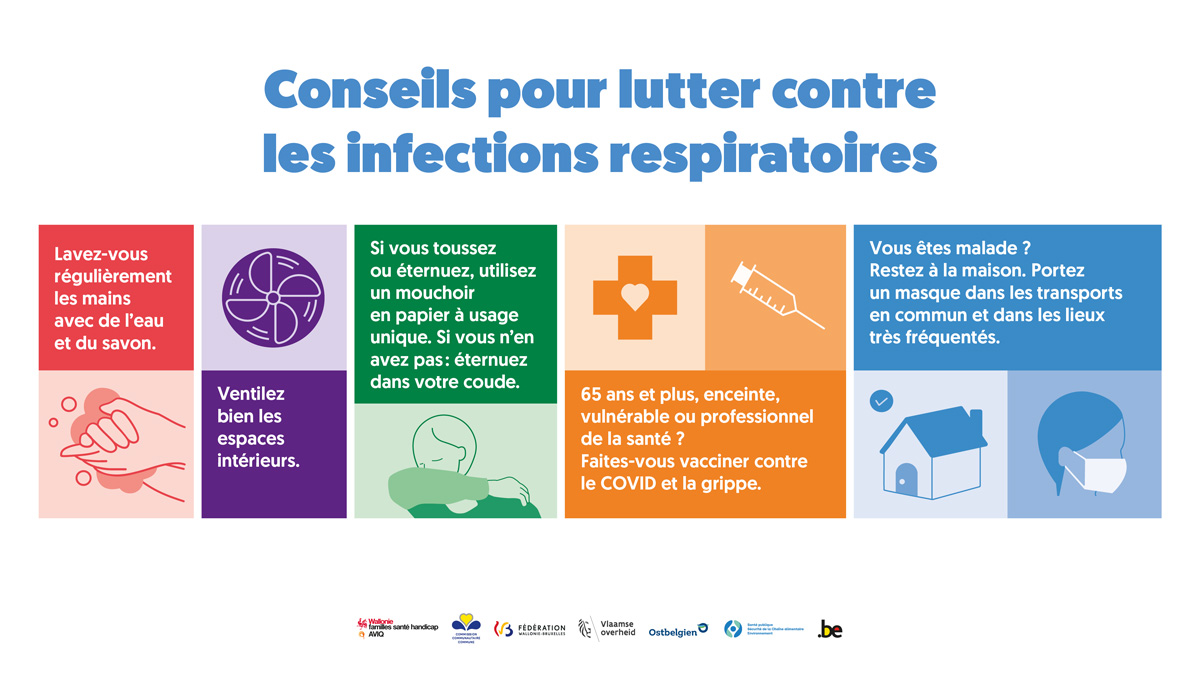

Maladie bénigne Les patients présentent une infection virale des voies respiratoires supérieures sans complications, et peuvent présenter des symptômes non spécifiques,.

Mars 2020 . Centre de traitement des infections respiratoires aiguës sévères . Manuel pratique pour la mise en place et la gestion d’un centre de traitement des IRAS et d’une.

meSoigner - Les infections respiratoires aiguës dans le monde